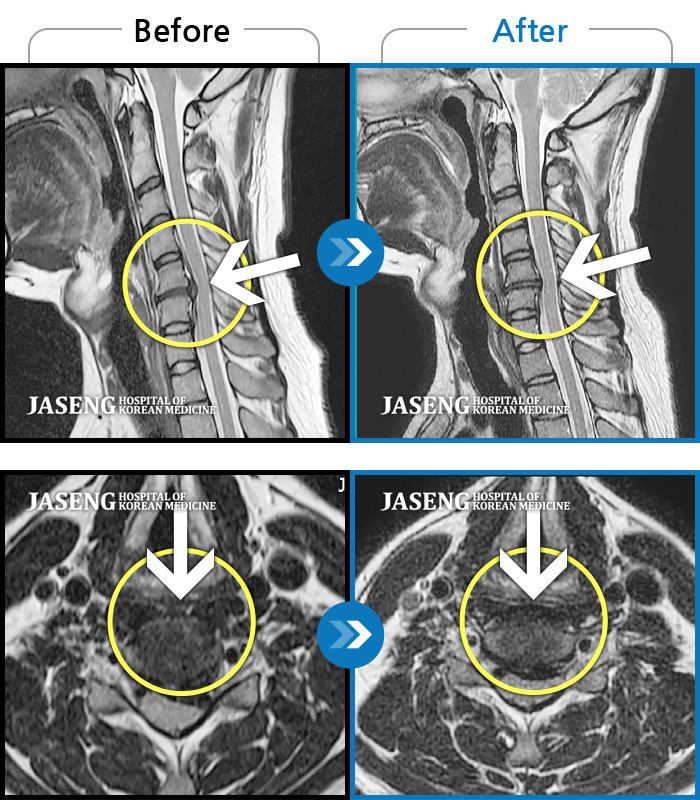

• 목디스크